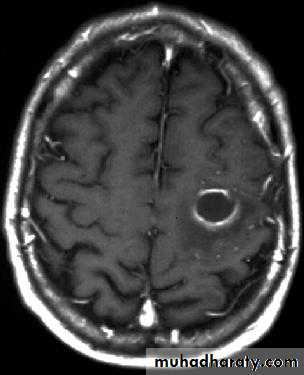

Brain Abscess MRI

• MRI is done with gadolinium enhancement.

• They will show a single (or multiple) space occupying lesion that is well delineated with an enhancing wall, with variable surrounding oedema.

• B. Radiological Investigations:• The differential diagnosis of a single brain abscess in CT or MRI is a solitary metastasis, primary brain tumour or cerebral infarction.